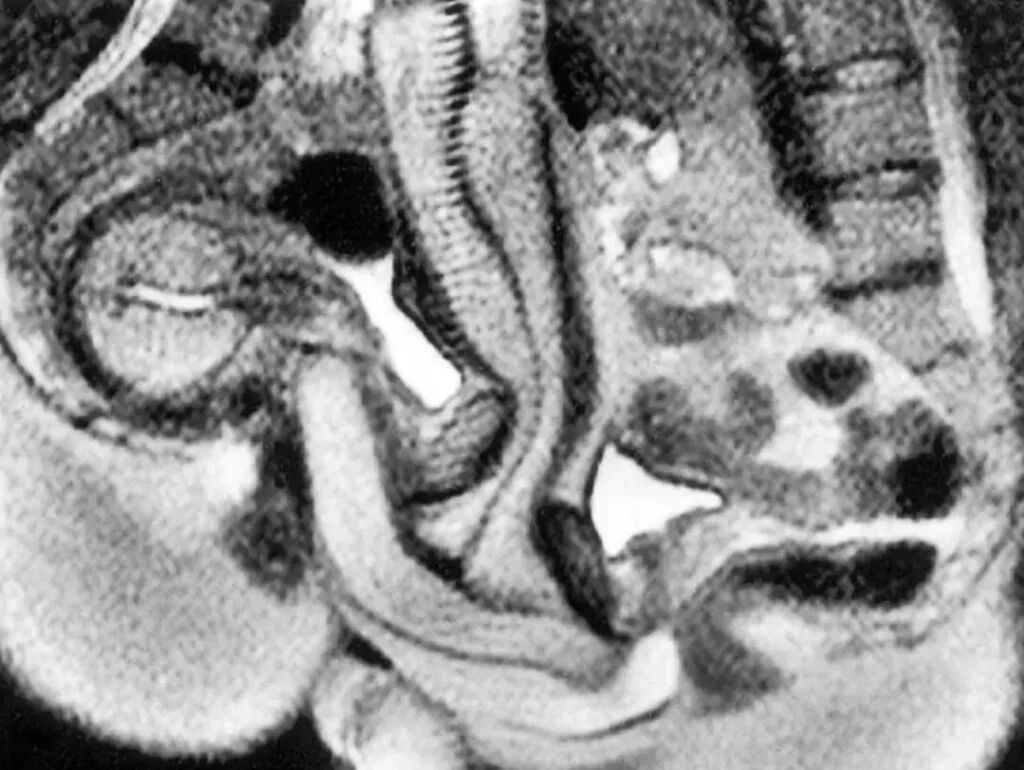

De uitkomst van het experiment was baanbrekend. Meer dan 500 jaar lang werd aangenomen dat het inwendige kanaal van het vrouwelijke voortplantingsstelsel een rechte, cilindervormige structuur had. Dat idee was gebaseerd op onder andere de anatomische schetsen van niemand minder dan Leonardo da Vinci. Indrukwekkend, maar dus niet geheel accuraat. De beelden van de scan toonden aan dat het kanaal in werkelijkheid gebogen is. Geen rechte lijn dus, maar een subtiele bocht.

Het mannelijk geslachtsdeel past zich vervolgens aan die natuurlijke kromming aan. Een eeuwenoude aanname over het vrouwelijk lichaam werd daarmee ontkracht. De beelden van het 25 jaar oude onderzoek zijn ook weer boven komen drijven, en die kun je hieronder bekijken: